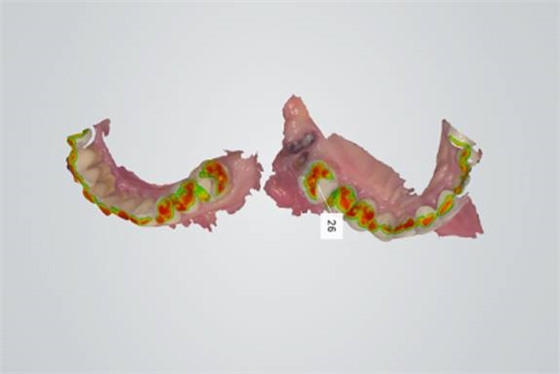

隨著數(shù)字化浪潮的發(fā)展,東營市文彬口腔門診部也緊跟數(shù)字化的腳步,特設立數(shù)字化掃描室,使用目前世界上主流的3shape公司生產(chǎn)的口內(nèi)掃描儀Trios獲取數(shù)字模型。

5.掃描效果如圖

6.檢查模型的倒凹情況和咬合空間是否充足